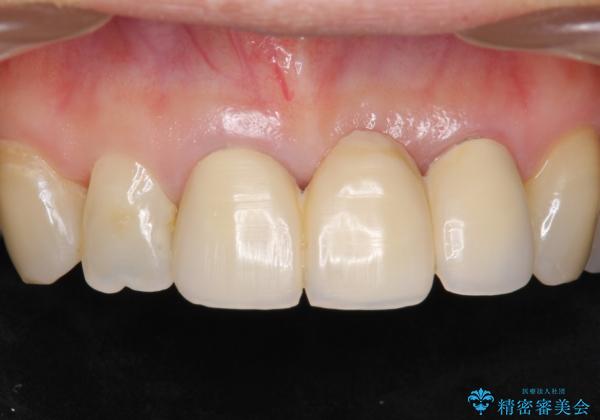

不自然なブリッジ 自然なセラミックでやりかえ 30代女性

前歯のレジン前装冠(保険内)によるブリッジは、金属で裏打ちされており透明感がなく不自然で、ポンティックも必要以上に長く作られていました。

古いブリッジと金属の土台を除去し、ファイバーコア(金属を使わない強くてしなやかな土台)を植立したのち、オールセラミックのブリッジによる補綴治療を行いました。。

自然な仕上がりに喜んで頂けました。

モチベーションが上がりオフィスホワイトニングもご希望され、口元の印象が明るくなりました。

クラウンの種類:オールセラミッククラウン スタンダード